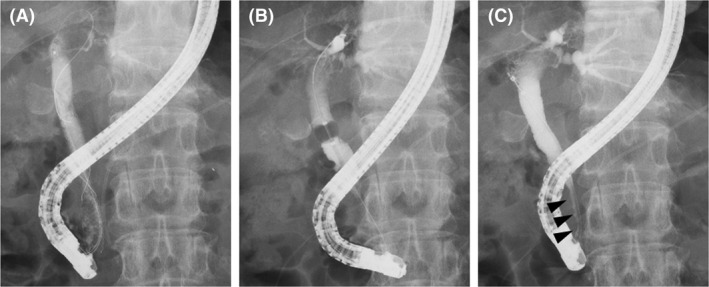

Endoscopic cholangiography was repeated a week after the first cholangiography. We observed that all the CBD stones detected in the initial cholangiography had disappeared spontaneously (Figure 3A). After the CSEMS removal, the biliary sludge was removed using a balloon catheter (Figure 3B). We confirmed that there were no stones in the CBD, and the stricture of the distal CBD showed slight improvement (Figure 3C). Finally, the pancreatic stent was removed.

The CSEMS should be placed for a longer duration to avoid recurrence of the CBD stones. Although CSEMS dilated the distal CBD stricture, the distal CBD remained thin (Figure 3C). In the previous reports, the duration and effectiveness of the CSEMS placement for CBD strictures secondary to CP were variable. Cahen et al20 reported six cases that received CSEMS for CBD stricture with CP. They reported the CSEMS removal time to be 3‐6 months and that 66% of the CBD strictures showed improvement. Lalezari et al21 reported a case with CP in which the CBD was dilated by CSEMS. In this report, the CSEMS was placed for 63 days, and the CBD stricture had improved. Haapamäki et al22 conducted a randomized controlled study on the effectiveness of multiple plastic stents vs the CSEMS in treating biliary stricture with CP. In this study, CSEMS was removed 6 months after randomization, and the 2‐year stricture‐free success rate was 92% (24/26). Although the targets were not CP patients alone, Park et al23 increased the duration of CSEMS placement to ≥120 days for resolution of the CBD stricture.